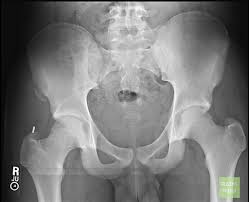

Anterior Superior Iliac Spine, Appendicular Skeleton And Joints Ppt Download : It can be palpated by putting the hands at the top of the hipbones and following the bony margins toward the front of the hips.. The posterior border of the ala, shorter than the anterior, also presents two projections separated by a notch, the posterior superior iliac spine and the posterior inferior iliac spine. Jun 28, 2021 · insertion: Asis, anterior superior iliac spine. Diagnosis is made with pelvis radiographs that shows an avulsion off the aiis. Anterior angulation of the coccyx may be a normal variant but poses a diagnostic challenge for those considering coccygeal trauma.

It provides attachment for the inguinal ligament , the sartorius muscle , 1 4 and the tensor fasciae latae muscle. The anterior superior iliac spine (asis) is the most anterior part of the iliac crest. An anterior superior iliac spine (asis) avulsion is a traumatic avulsion of the asis due to a sudden and forceful contraction of the sartorius and tensor fascia lata that occurs in young athletes. Asis, anterior superior iliac spine. This part is the most observable and palpable of the pelvis. The posterior border of the ala, shorter than the anterior, also presents two projections separated by a notch, the posterior superior iliac spine and the posterior inferior iliac spine. Diagnosis is made radiographically with displaced injuries but ct/mri may be required to diagnosis nondisplaced fractures. It provides attachment for the inguinal ligament, and the sartorius muscle. An anterior inferior iliac spine (aiis) avulsion is an apophyseal avulsion injury seen in adolescent athletes as a result of eccentric contraction of the rectus femoris. It refers to the anterior extremity of the iliac crest of the pelvis. The anterior superior iliac spine refers to the anterior extremity of the iliac crest of the pelvis. Outer lip of anterior iliac crest, anterior superior iliac spine (asis) insertion: Classification four types of coccyx have been described:

The posterior border of the ala, shorter than the anterior, also presents two projections separated by a notch, the posterior superior iliac spine and the posterior inferior iliac spine. Aug 29, 2017 · aiis, anterior inferior iliac spine; It refers to the anterior extremity of the iliac crest of the pelvis. The anterior superior iliac spine refers to the anterior extremity of the iliac crest of the pelvis. Many different muscles of the trunk and thigh attach to the iliac crest. Thigh abduction, thigh internal rotation (anterior part); Anterior angulation of the coccyx may be a normal variant but poses a diagnostic challenge for those considering coccygeal trauma. Asis, anterior superior iliac spine.

Outer lip of anterior iliac crest, anterior superior iliac spine (asis) insertion: Aug 29, 2017 · aiis, anterior inferior iliac spine; Asis, anterior superior iliac spine. The posterior border of the ala, shorter than the anterior, also presents two projections separated by a notch, the posterior superior iliac spine and the posterior inferior iliac spine. An anterior superior iliac spine (asis) avulsion is a traumatic avulsion of the asis due to a sudden and forceful contraction of the sartorius and tensor fascia lata that occurs in young athletes. The tensor fasciae latae and sartorius muscles of the thigh have their origins at the anterior superior spine. An anterior inferior iliac spine (aiis) avulsion is an apophyseal avulsion injury seen in adolescent athletes as a result of eccentric contraction of the rectus femoris. It provides attachment for the inguinal ligament, and the sartorius muscle. The posterior superior iliac spine serves for the attachment of the oblique portion of the posterior sacroiliac ligaments and the multifidus. It provides attachment for the inguinal ligament , the sartorius muscle , 1 4 and the tensor fasciae latae muscle. It can be palpated by putting the hands at the top of the hipbones and following the bony margins toward the front of the hips. Classification four types of coccyx have been described: Diagnosis is made radiographically with displaced injuries but ct/mri may be required to diagnosis nondisplaced fractures.